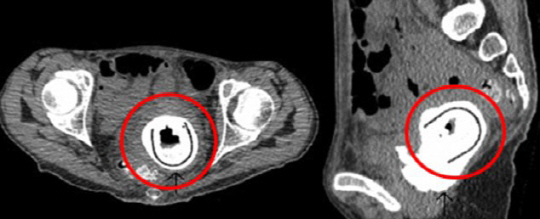

여성의 몸 안쪽에 둘레 길이가 약 12㎝에 달하는 타원형 형태의 자위 용품이 있었던 것.

의료진의 설명을 들은 여성은 10년간 그 용품을 사용한 적이 없다고 펄쩍 뒤었다. 하지만 병원 관계자는 "그녀가 술에 취한채 파트너와 즐기다가 깜빡 잊고 기구를 빼내지 않은 것으로 보인다"고 의심했다.